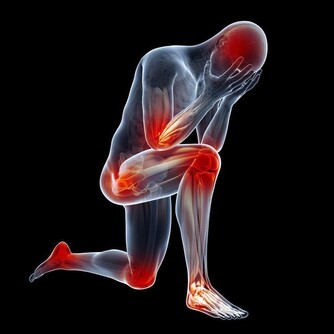

腳是人體的另一個心臟,腳雖然距離心臟較遠,但是其對心臟的健康卻是非常重要的存在。

血液從心臟流到腳部的時候,由於其處於人體末端,所以血液想要重新回到心臟會有所阻礙。

但是,人類得天獨厚的走路方式,可以促使血液循環加速,幫助血液回流至心臟。

所以,我們可以從腳部看出心臟的健康隱患。

腳上出現這物,竟是心臟病信號。腳部出現青筋腳面部位本來是平坦無皺紋的,如果表面出錢青筋凸起,說明腳部的血液循環開始出現受阻現象。

雖然身體暫時感覺不到其他的不適癥狀,但是我們千萬不可以忽視這一癥狀。

往往大病之前總是潛伏著一些小毛病。